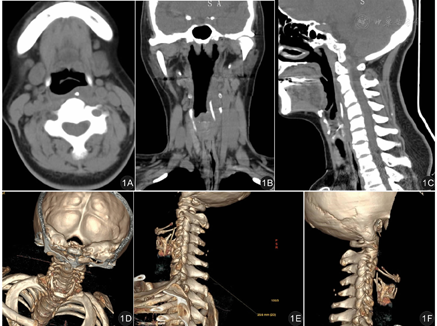

患者,女,52岁,因"误吞鱼刺2 d"收入院。查体:患者生命体征平稳,口咽部黏膜无充血异常,喉咽部黏膜稍有肿胀,未见明显异物残端。喉镜下咽喉各壁未见异物征象,损伤痕迹不明显。颈部CT平扫+三维重建示:平扫示咽部偏左侧(约会厌平面至环状软骨平面)见纵行线状高密度影,周围软组织肿胀。食管上段显示尚清,未见明显异常。见图1。